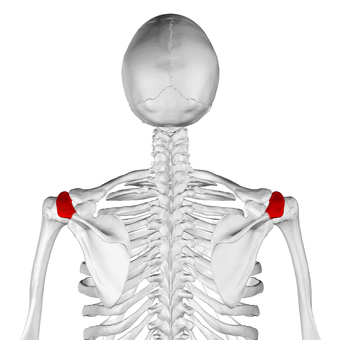

عظم الكتف الأيسر. صورة أمامية. يظهر الأخرم باللون الأحمر.

Acromion of scapula06.png

الأخرم (من اليونانية: أكروس، "الأعلى" ōmos، "الكتف"، المفرد: acromia)، هو نتوء عظمي على عظمة الكتف (لوحة الكتف). يمتد الأخرم والناتئ الغرابى جانبياً معاً فوق المفصل الحقاني العضدي. يتمفصل الأخرم مع الترقوة ليكوّنا المفصل الأخرمي الترقوي.

الأخرم يشكل قمة الكتف، وهو نتوء كبير، شكله مثلث إلى حد ما أو مستطيل، مفلطح من الخلف إلى الأمام، يبرز أوله وحشياُ، ثم يتقوس إلى الأمام و إلى الأعلى، ثم يتعلق مشرفا على التجويف الحقاني.[1]